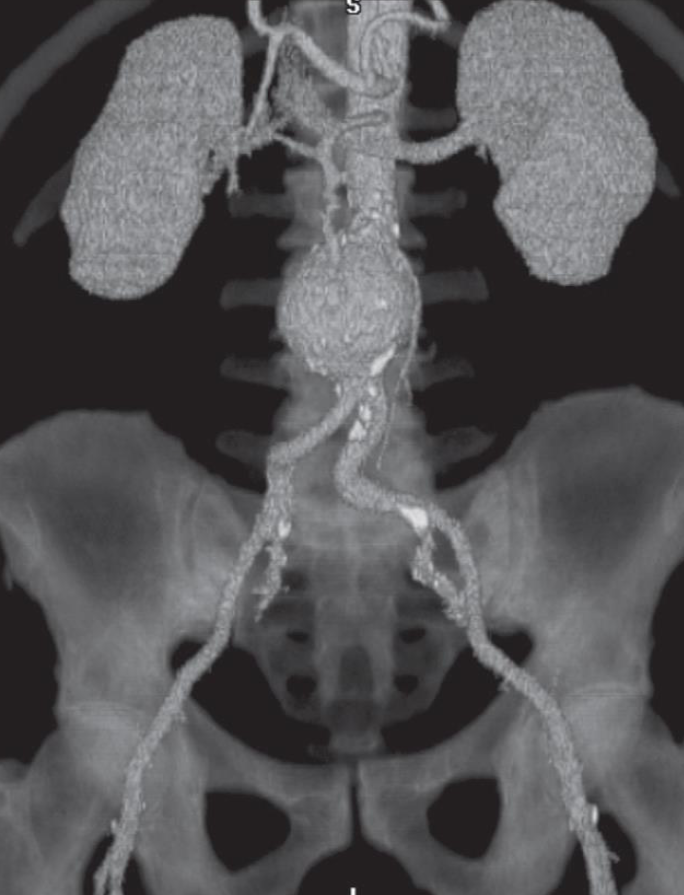

A. Give the name of the imaging examination in the given image. CTU

B. Give the NAMES of the used contrast media for the examination Iodide Contrast Media